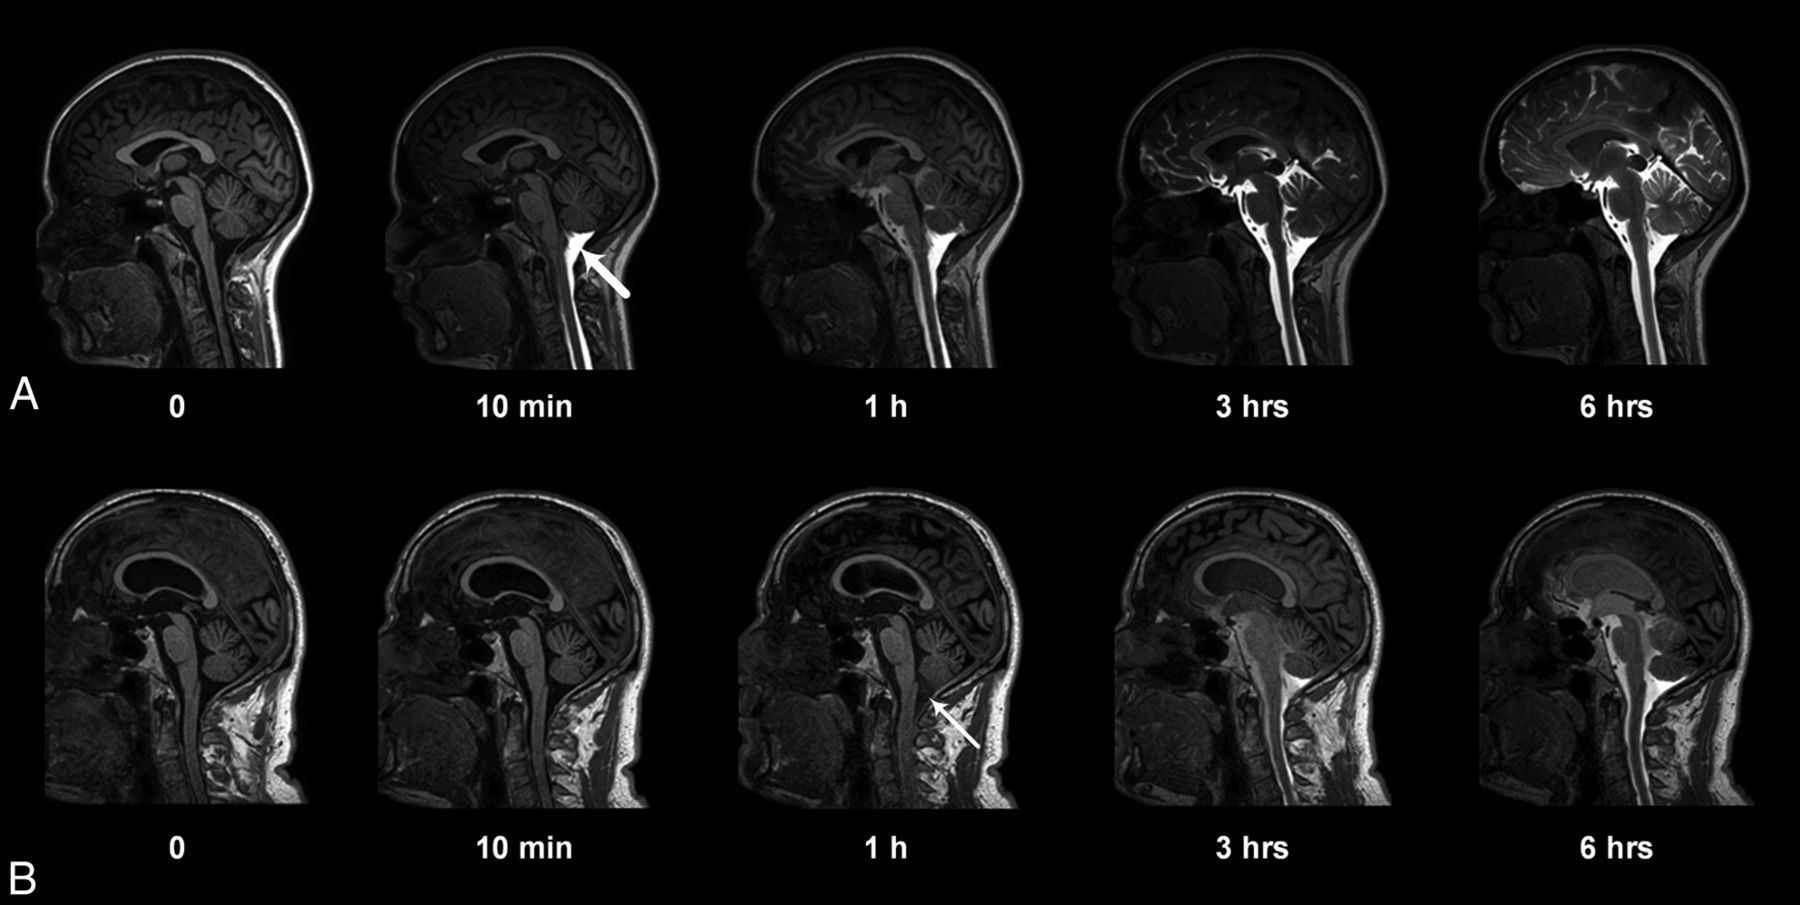

Entry of gadobutrol into the CSF within the intracranial compartment at consecutive MR imaging of a patient with a pineal gland cyst (A) and iNPH (B). Intrathecal administration of 0.5 mL (1.0 mmol/mL) of gadobutrol at the lower lumbar level was preceded by unenhanced, T1-weighted MR imaging (time point zero). After the correct needle position had been verified at fluoroscopy by injection of 3 mL of iohexanol (270 mg I/mL), the patient was transported in the supine position to the MR imaging suite next door, and acquisition of identical, consecutive T1 scans was initiated immediately and performed continuously within the first hour. Typically, the contrast agent had reached the cisterna magna at the first postcontrast scan obtained after approximately 10 minutes (A, thick arrow). In some patients, however, enhancement occurred much later, as in B, where slight enhancement was first depicted at 1 hour (thin arrow). At 6-hour scans, gadobutrol is distributed widely in the CSF of both patients, but less prominently in B, where ventricular reflux can also be noted.